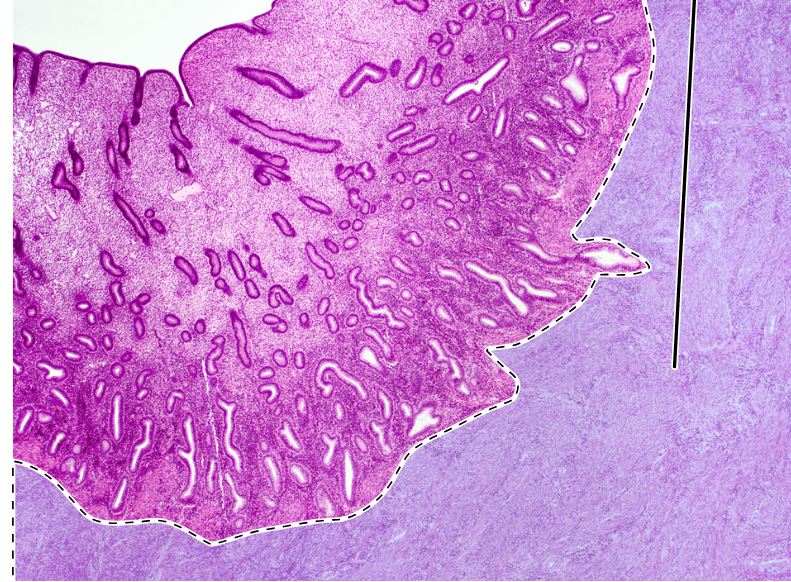

uterus

endometrium

uterine glands

myometrium